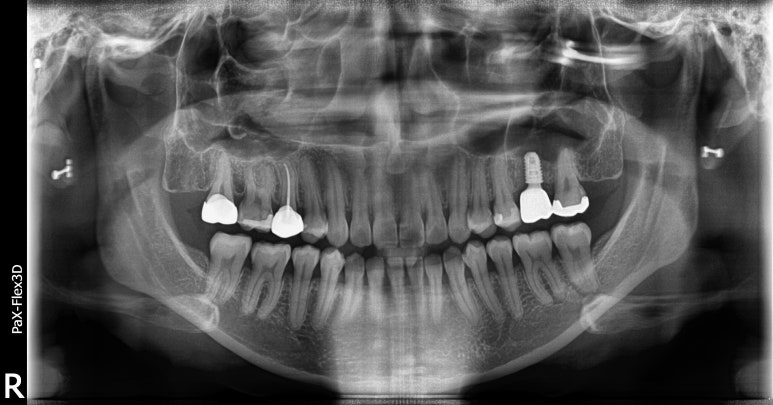

20대임플란트 실제 사례

25세 여성

(전) 2022-03-03 (후) 2022-10-11